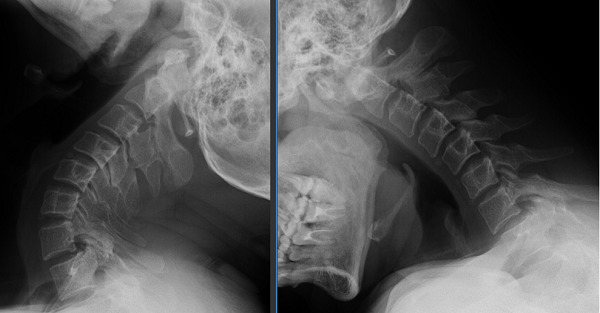

46岁的贾先生曾为此走了不少弯路,反复吃药、针灸都只能暂时缓解。最近一个月,症状加重,他经朋友介绍来到玉溪市人民医院骨外一科就诊。根据贾先生的病情描述,骨外一科接诊医师对其进行了详细的体格检查,并开具了相关检查,确诊为寰枢关节脱位(A型颅底凹陷),还合并寰椎发育畸形。

图片1

针对贾先生的病情,骨外一科柏涛主任团队进行了细致地讨论,个性化制定了贾先生的围手术期管理、手术方案包括:寰枢关节脱位复位技巧、固定节段的选择、植骨方式的选择。最终决定采用北医三院王超教授发明的方法:大重量牵引、压板复位、钉板系统固定、取自体髂骨进行中线植骨施行手术。